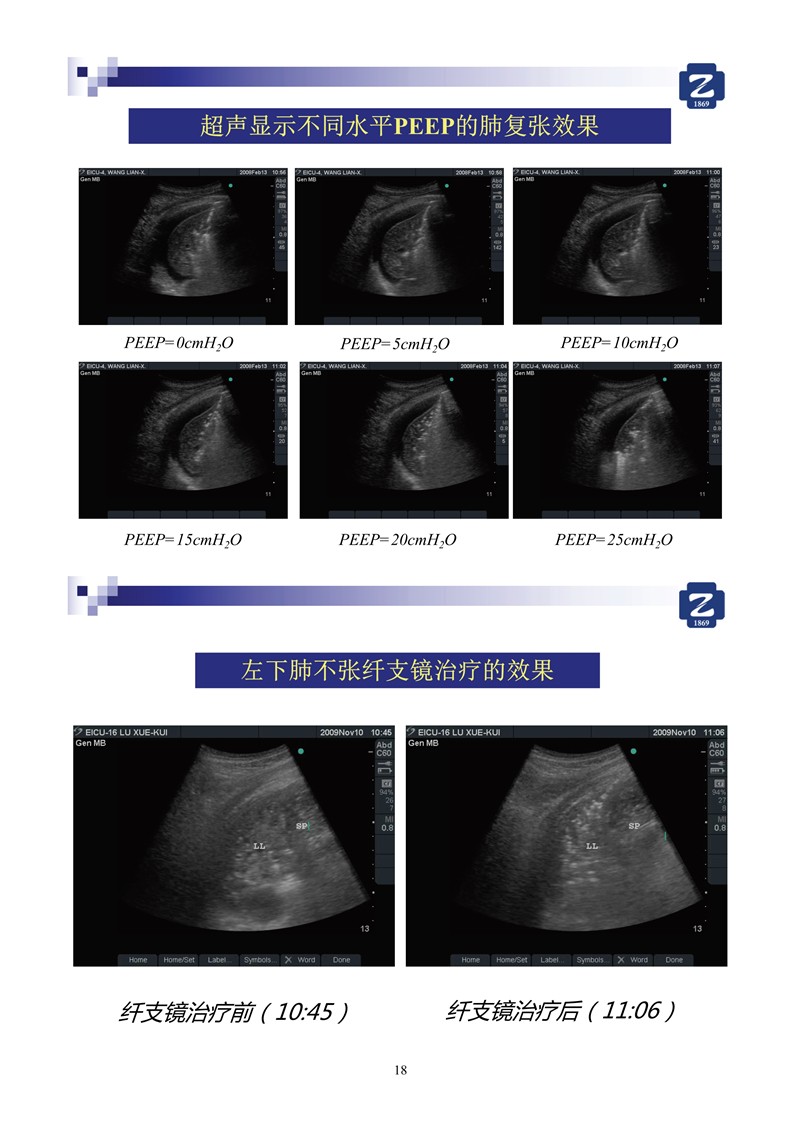

第二版新型冠狀病毒肺炎超聲診斷實(shí)用手冊(cè)_64.jpg